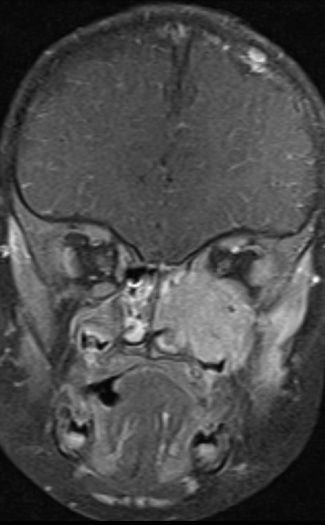

On imaging presentation is variable but it typically presents as a lytic defect most commonly seen in superotemporal orbit or sphenoid wing. The LCH disorders have a predilection for hematopoietically active bone marrow so this is why it is seen in the supero-temporal orbit quite commonly. LCH lesions enhanced only minimally with contrast on CT. On T1-weighted MRI images typically showed soft tissue masses with signal intensity similar to muscle, and enhances well with fat-suppression and gadolinunium. [10] The histological diagnosis of LCH lesions is based on staining for S-100 protein and CD1a antigen or finding Birbeck granules (shaped like tennis racquets) on electron microscopy.[11][12]

It is suggested by others that it is important to distinguish between lesions in the orbital bones with intracranial soft tissue extension verus simple and easily accessible orbital lesions without a prominent retroorbital or intracranial soft tissue component. Lesions with a prominent retroorbital or intracranial soft tissue component can be regarded as CNS-Risk lesions which mandate systemic therapy under the International Treatment Protocol for systemic/multifocal Langerhans Cell Histiocytosis (LCH-III) . They suggest that chemotherapy with vinblastine and prednisone, as offered in the LCH-III protocol, may be the less invasive strategy in extended infiltrative lesions or in lesions that fail to regress after initial biopsy (Grois and Gadner, 2004).[23][24]